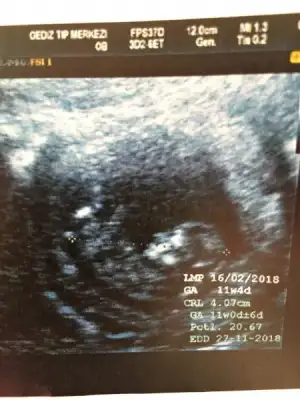

Merhaba kızlar bizde 11+4 olduk nasipse cinsiyet için doktor daha erken dedi ama tahminlerinizi yazarsanız çok sevinirimmm :anneadayı::KK200::emir_bebek:

Eklentiler

• image.webp

image.webp

22,1 KB · Görüntüleme: 69